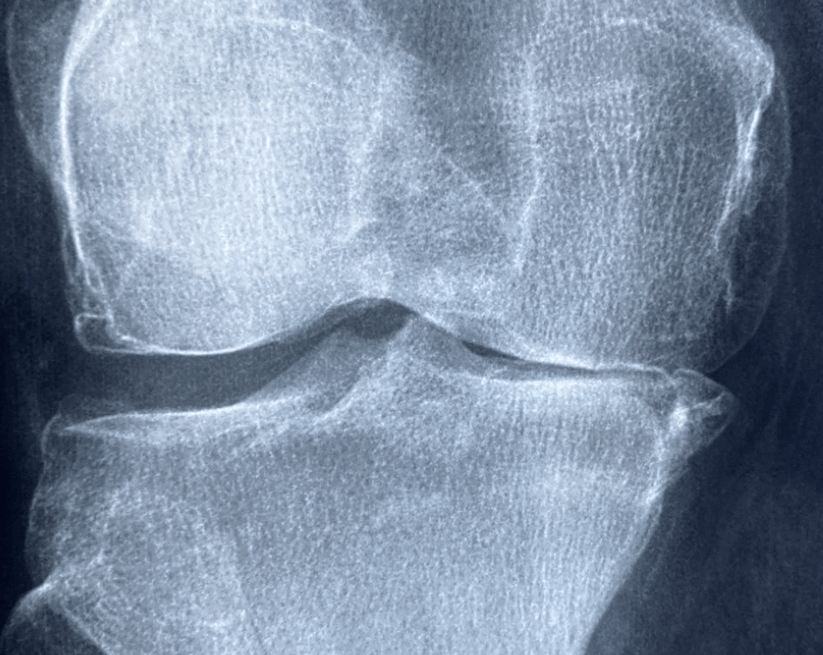

🦵 무릎이 아픈데, 운동만으로 충분할까요?

무릎 통증을 줄이기 위해선 운동도 중요하지만, 필수 영양소 보충도 반드시 필요합니다.